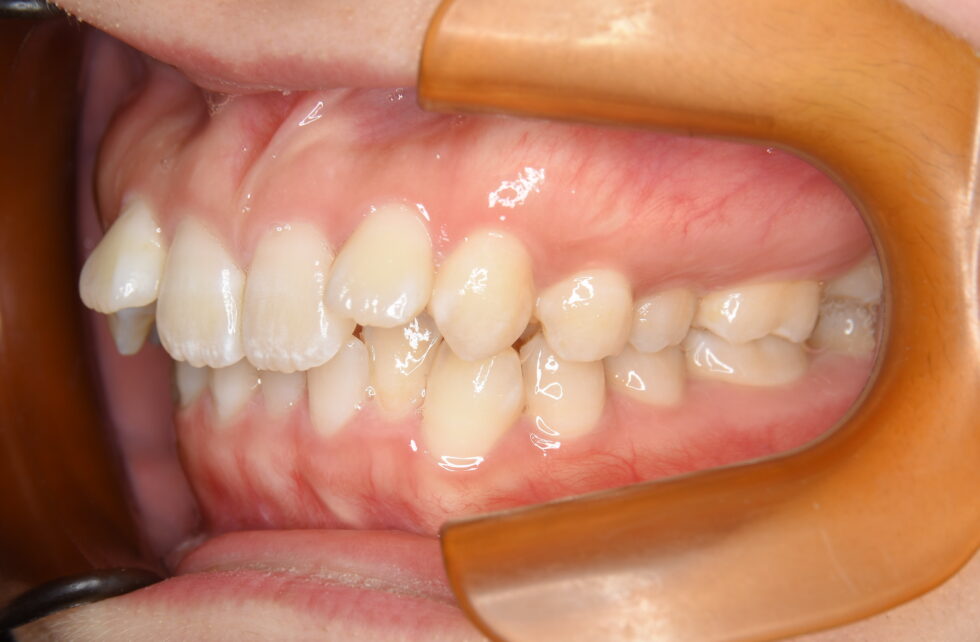

初診時年齢19歳の女性 上下顎前歯部の叢生を主訴にご来院いただいた。

上顎左右側側切歯が唇側転位となり下顎前歯も前後にずれてデコボコに生えていた。また、臼歯部は下あごの奥歯より上あごの奥歯が前方にかみ合っていた。